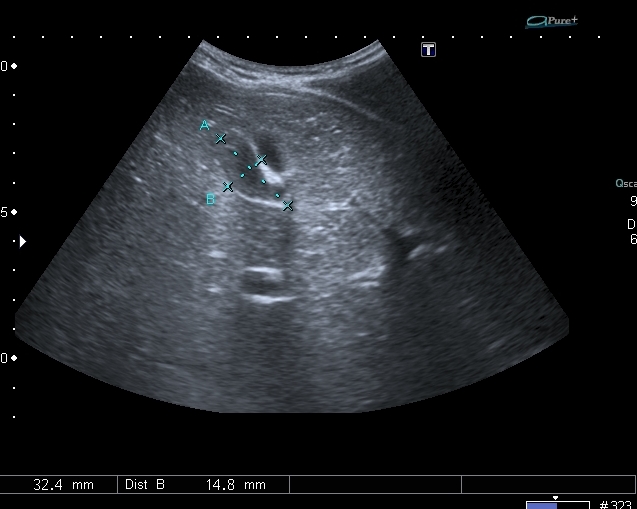

На УЗИ рядом с желчным пузырём определяется овоидное образование солидной струкутры с чёткими контурами.

При ЦДК кровоток в образовании не регистрировался, свободной жидкости в брюшной полости не было.